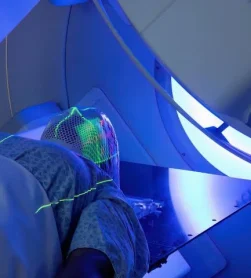

پرتودرمانی (رادیوتراپی)

· پرتودرمانی با شدت تعدیل شده: IMRT پس از جراحی در صورتی که همه تومر برداشته نشده باشد یا سلول های سرطانی درحاشیه توده سرطانی برداشته شده دیده شوند یا در مراحل پیشرفته برای از بین بردن سلولهای سرطانی باقیمانده استفاده میشود.

· برخی اوقات که توده سرطانی سایز بزرگی دارد رادیوتراپی برای کوچک کردن سایز تومور قبل از جراحی انجام میشود.

· براکیتراپی: کاشت منابع پرتوزا در ناحیه تومور (معمولاً در سرطان لب یا حفره دهان) برای رساندن دقیق دُز بالای اشعه به ضایعه ممکن است طبق نظر انکولوژیست انجام شود.